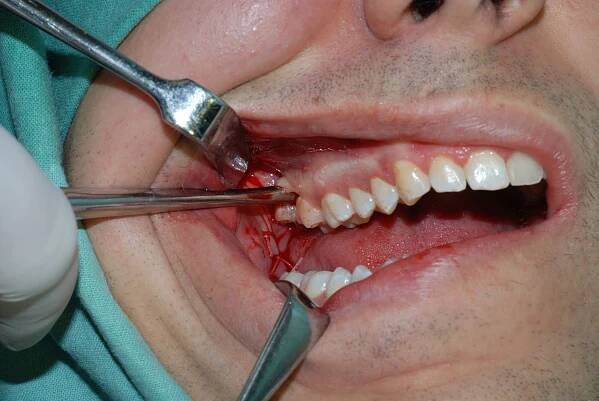

Existuje několik zákroků, které byste v zubařském křesle jen těžko čekali. Transplantace je bezpochyby jeden z nich. V jakých situacích se k takovému zásahu stomatolog uchýlí? Jak celá operace probíhá a jaká jsou rizika?

Transplantace krůtí dásně : Cena a postup

Gumový štěp